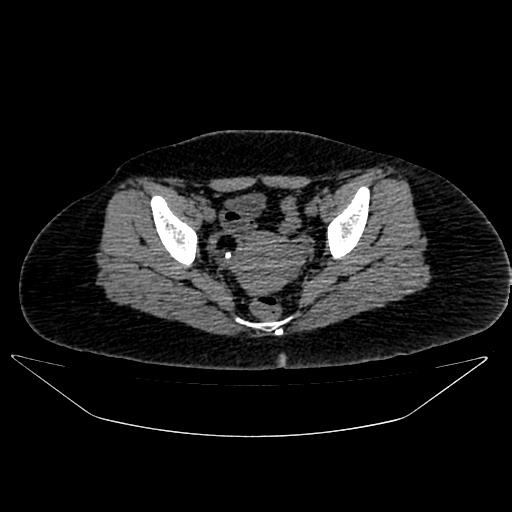

A 48 y old female presented with the complaint of irregular menses for the last 6 mo. The patient came to visit the gynecology OPD. The patient underwent abdominal and pelvic ultrasonography, which showed a subserosal fibroid and a normal-sized right ovary with an internal echogenic focus. Bilateral fallopian tubes and the other ovary were unremarkable. No free fluid was found on ultrasonography. The contrast CT scan shows (fig. 1) a normal-sized right ovary with a fat attenuation lesion and internal eccentric calcification. Routine blood hemogram along with thyroid and heart examination, were normal. On physical examination, no organomegaly was found.

Fig. 1: Normal-sized right ovary with a fat attenuation lesion and internal eccentric calcification